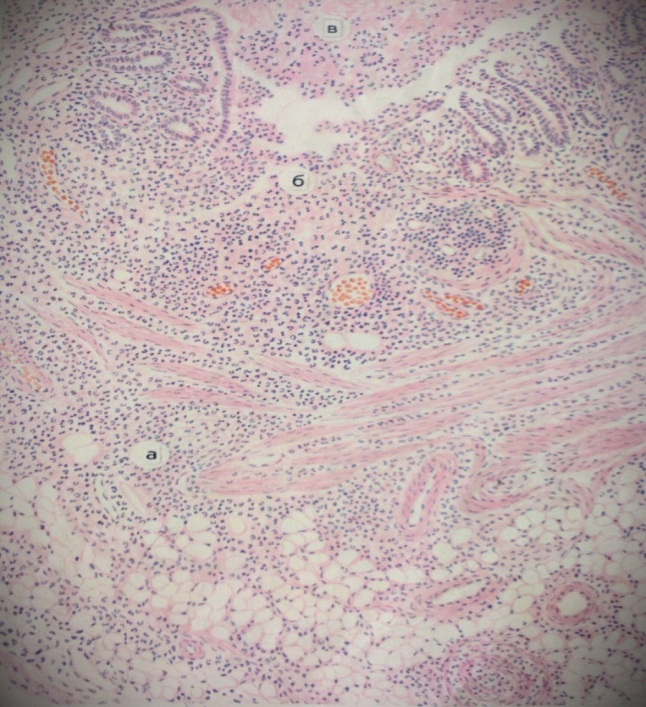

Карнификация Легкого: Микропрепараты и Диагностика

Раздел: Калейдоскоп образов